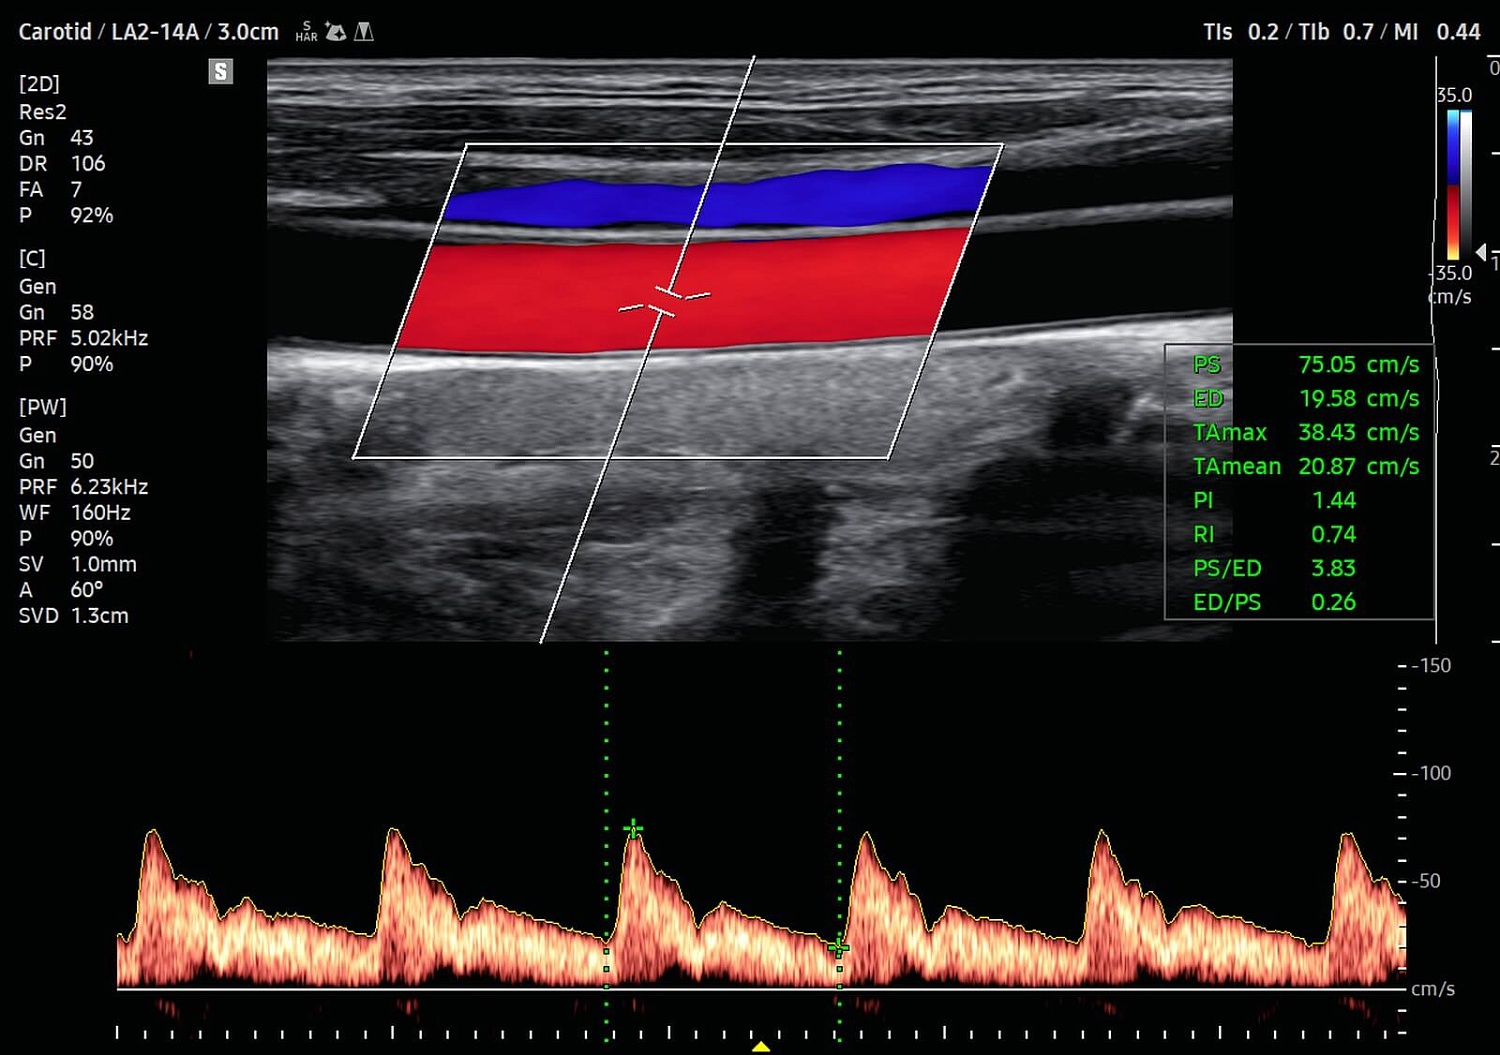

УЗИ аппарат V8 отличается превосходным технологическим оснащением, высочайшим уровнем визуализации и удобством использования. Многочисленные решения позволяют оптимизировать рутинный диагностический процесс, автоматически осуществляя измерения, расчеты и классифицируя выявленные изменения. Это значительно сокращает время на исследование и в разы повышает диагностическую точность. Помимо уже знакомых функций Biometry Assist, AutoIMT, 2D Follicle, 2DNT и пр., в модели реализована опция автоматического сегментирования структур сердца, автоизмерения с технологией Heart Assist, определение положения срединного нерва в поперечном сечении Nerve Track.

- измерение жесткости сосудов и оценку параметров прохождения пульсовой волны и пр.